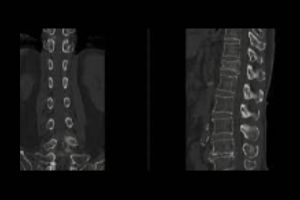

What is a CT Head and Left Orbit scan?

A CT Head and Left Orbit scan is a specialised imaging test that uses computed tomography (CT) technology to produce detailed cross-sectional images of the head and the left eye socket (orbit). This scan helps evaluate the bones, brain, soft tissues, and structures within and around the left eye. It is commonly used to detect abnormalities such as fractures, tumours, infections, bleeding, or foreign bodies in specified areas. The test is non-invasive and may involve the use of a contrast agent to enhance the visualisation of blood vessels and specific tissues. It is often ordered in cases of trauma, neurological symptoms, or eye-related concerns.

What is the Procedure for CT Head and Left Orbit?

The procedure for a CT Head and Left Orbit generally involves the following steps:

- You will lie on a motorised table that moves into the CT scanner.

- Your head will be positioned and may be secured to prevent movement.

- The technician will leave the room but will monitor you and communicate via an intercom.

- The scanner rotates and takes detailed X-ray images of your head and left orbit.

- If contrast dye is required, it may be injected into a vein in your arm before the scan.

- You will need to stay still and may be asked to hold your breath for a few seconds during imaging.

- The procedure is quick and painless, usually completed within 10–20 minutes.